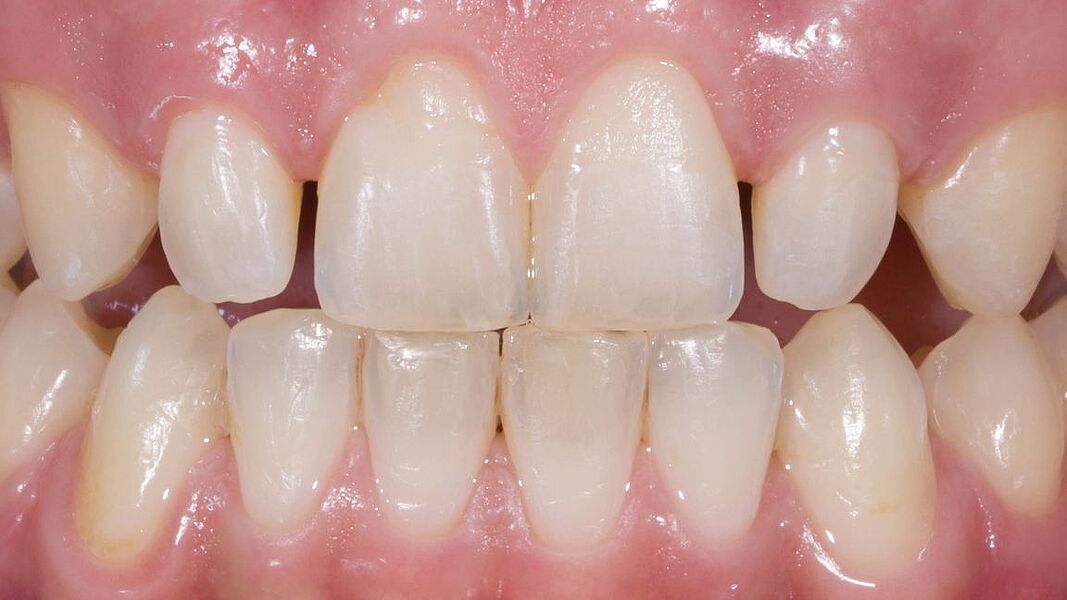

Im Journal Zahnmedizin up2date demonstrieren unsere Ästhetik-Spezialisten in einem weiteren Beitrag zum Thema professionelle Zahnaufhellung wie ein entsprechend angeleitetes At-Home-Bleaching funktioniert. Die entscheidende Vorbereitungsphase mit der Herstellung der Schienen und der adäquaten Instruktion des Patienten werden in dieser Publikation anhand eines Bildessays illustriert.

In der Ausgabe 02/2023 der Fachzeitschrift Zahnmedizin up2date berichten unsere beiden Ästhetik-Spezialisten wie ein professionelles In-Office-Bleaching vitaler Zähne funktionieren kann. Die hierzu nötigen Arbeitsschritte einschließlich der klinischen Voraussetzungen werden Schritt für Schritt anhand eines Bildessays illustriert.

Was ist vertretbar, was nicht? Diesen Fragen gehen die drei Autoren dieses im Quintessenz Team-Journal publizierten Fachbeitrags nach. Den Hintergrund bildet, dass aktuell vermehrt Patientinnen und Patienten nach einer Zahnaufhellung nachfragen. Ein strahlend weißes Lächeln steht offensichtlich nicht nur für Gesundheit und Schönheit, sondern wird auch mit Erfolg verbunden. Dabei haben an dem derzeitigen Wunsch nach helleren Zähnen sicherlich die während der Coronapandemie häufig stattfindenden Videokonferenzen ihren Anteil, bei denen – sofern natürlich die Videokamera eingeschaltet ist – das Erscheinungsbild des Gesichts noch mehr in den Vordergrund rückt. Die Autoren zeigen anhand Bilderserien die Anwendungsmöglichkeiten der professionellen Zahnaufhellung, geben Hinweise zu Grenzbereichen und ziehen Grenzen. Klar ist: Richtig angewandt, ist die professionelle Zahnaufhellung ein sicheres und effektives Verfahren.